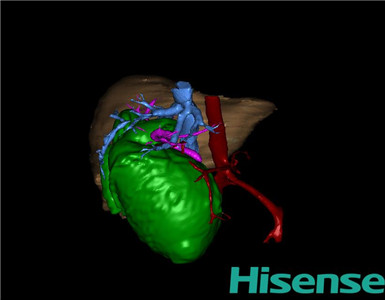

术前三维重建及手术方案设计:

将0.625mm双源薄层CT资料的静脉期和动脉期Dicom格式文件导入海信CAS系统。

通过调节窗宽窗位调整CT序号,对肝实质,胆囊,胆总管,下腔静脉,肝动脉、门静脉及肝静脉等进行三维重建;系统自动计算肝脏体积。

术前手术方案的规划。

术前三维重建:

重建图片